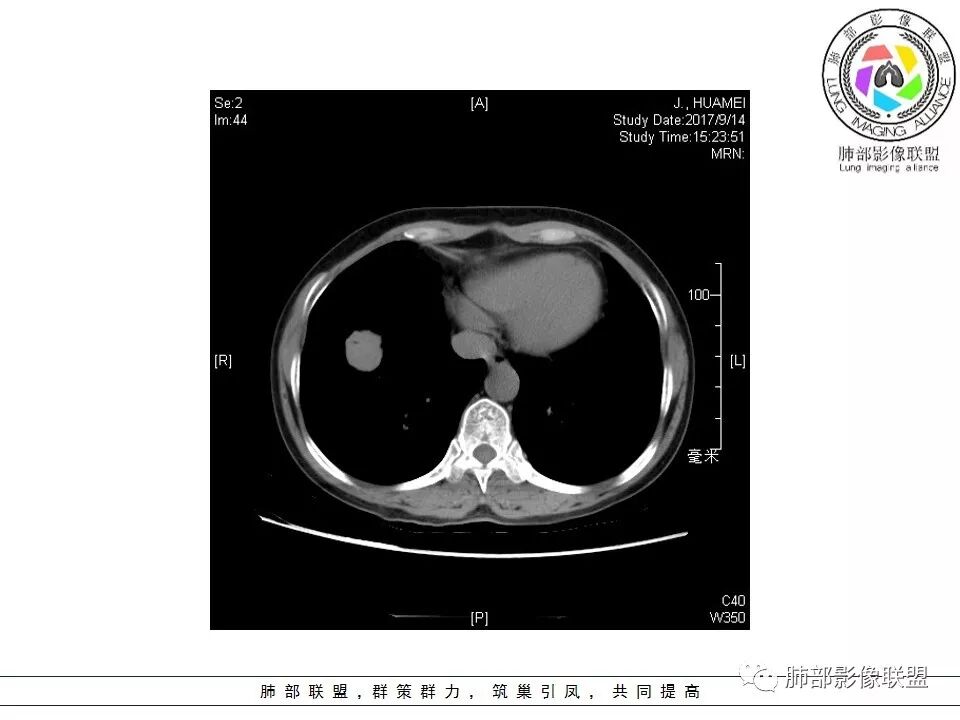

患者中年女性,因“体检发现右下肺占位4天。”入院,肿瘤标记物NSE轻高。

胸CT:右肺下叶前基底段占位性病变,内可见支气管穿过,病灶边缘不规则,呈浅分叶,未见明显毛刺。纵隔窗可见病灶密度相对均匀,增强可见病灶强化,内可见血管增粗,边缘模糊,总体考虑恶性,腺?。良性疾病鉴别错构。

南边老师分析

这个病灶边缘还是有一点点恶性征象,有分叶,似乎有点地方还有一些小毛刺样感觉

部分区域整体以膨隆为主,部分区域稍收缩

内部支气管走形非常自然,达远端稍扩张;内部血管穿行也非常自然

内部密度比较均匀,我们一般来说,首先良性肿瘤不支持,因为它里面的血管走形太自然了;然后就是炎性病变跟恶性肿瘤,但是它的边缘膨隆比较厉害,有些地方还毛刺,不是很清楚,倾向一个恶性病变

恶性的血管穿行自然,包括支气管稍扩张,最常见还是淋巴瘤,它强化比较均匀;

粘液腺癌一般支气管扩张比较罕见,这个密度及强化太均匀,不是很符合,所以把淋巴瘤放前面,癌待排;

方向定在恶性的,炎性病变不是很符合

结果:粘膜相关淋巴组织结外边缘区B细胞淋巴瘤